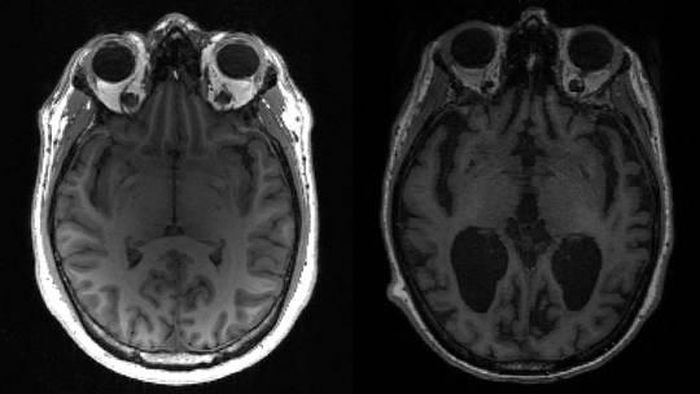

Ảnh chụp não những thanh niên được tin mắc bệnh thần kinh lạ ở New Brunswick, Canada. Ảnh: Alamy

Một bà mẹ trẻ cũng nhanh chóng sụt gần 60 cân, mắc chứng mất ngủ và bắt đầu bị ảo giác. Hình ảnh chụp não của cô cho thấy các dấu hiệu đang phát triển bệnh teo não.